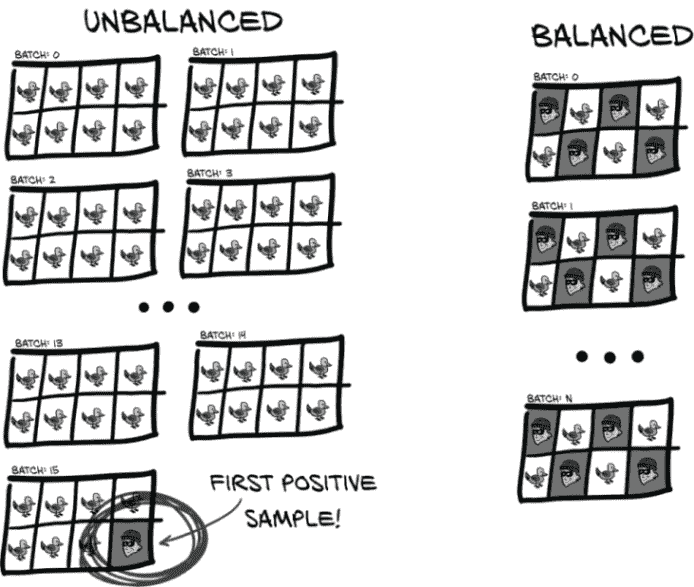

这里的关键是:1 组和 4 组可以是任意大小,它们对训练几乎没有影响。唯一重要的是 2 组和 3 组能够相互抵消,防止网络崩溃到退化的“只输出一种结果”的状态。由于 2 组比 3 组大 500 倍,我们使用的批量大小为 32,大约需要经过 500/32 = 15 批次才能看到一个正样本。这意味着 15 个训练批次中有 14 个将是 100%负面的,只会将所有模型权重拉向预测负面的方向。这种不平衡的拉力产生了我们一直看到的退化行为。

相反,我们希望正样本和负样本数量相同。因此,在训练的第一部分中,一半的标签将被错误分类,这意味着第 2 组和第 3 组的大小应该大致相等。我们还希望确保我们呈现的批次中包含负样本和正样本的混合。平衡将导致拉锯战平衡,每个批次中的类别混合将使模型有很好的机会学会区分这两个类别。由于我们的 LUNA 数据只有少量固定数量的正样本,我们将不得不接受我们拥有的正样本并在训练期间重复呈现它们。

显然,正确的方法是以一种不允许学生利用测试的更大结构来回答问题的方式交替真实和错误答案。虽然学生可能会注意到“奇数问题是真实的,偶数问题是错误的”这样的模式,但 PyTorch 使用的批处理系统不允许模型“注意到”或利用那种模式。我们的训练数据集将需要更新,以在正样本和负样本之间交替,就像图 12.17 中那样。

不平衡数据就像我们在第九章开始提到的草堆中的针。如果您必须手动执行这项分类工作,您可能会开始同情普雷斯顿。

图 12.17 不平衡数据的批次将在第一个正事件之前只有负事件,而平衡数据可以每隔一个样本交替出现。

然而,我们不会为验证进行任何平衡。我们的模型需要在现实世界中表现良好,而现实世界是不平衡的(毕竟,这就是我们获取原始数据的地方!)。